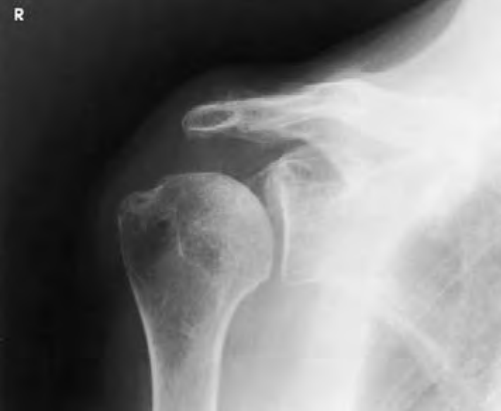

안녕하세요, 오늘은 어깨(shoulder) 촬영방법 중 하나인 shoulder true AP(GRASHEY METHOD) 촬영법에 대해서 설명하겠습니다. 견관절의 병리학적 상태 혹은 외상에 의한 골절, 탈구나 손상을 전체적으로 확인하는데 유용한 검사입니다. 특히 Glenoid cavity(접시오목, 관절와강) 관찰에 용이합니다. 그럼 이미지를 보면서 설명 시작하겠습니다.

Shoulder TRUE AP (GRASHEY METHOD)

- Humeral head(상완골두)와 Glenoid cavity(관절와강) 사이의 공간이 잘 보여야 한다.

- 관절의 연부조직과 glenoid cavity, humeral head의 세부 정보가 보여야 한다.